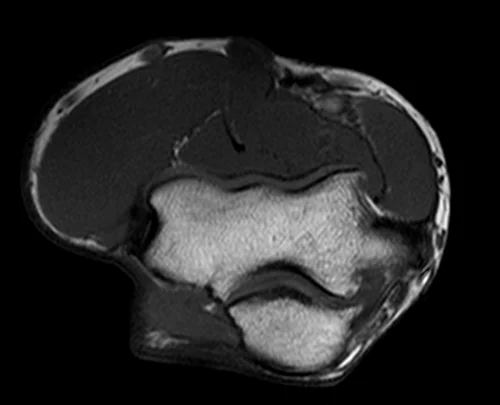

mri elbow axial t1 image 3 - MRI